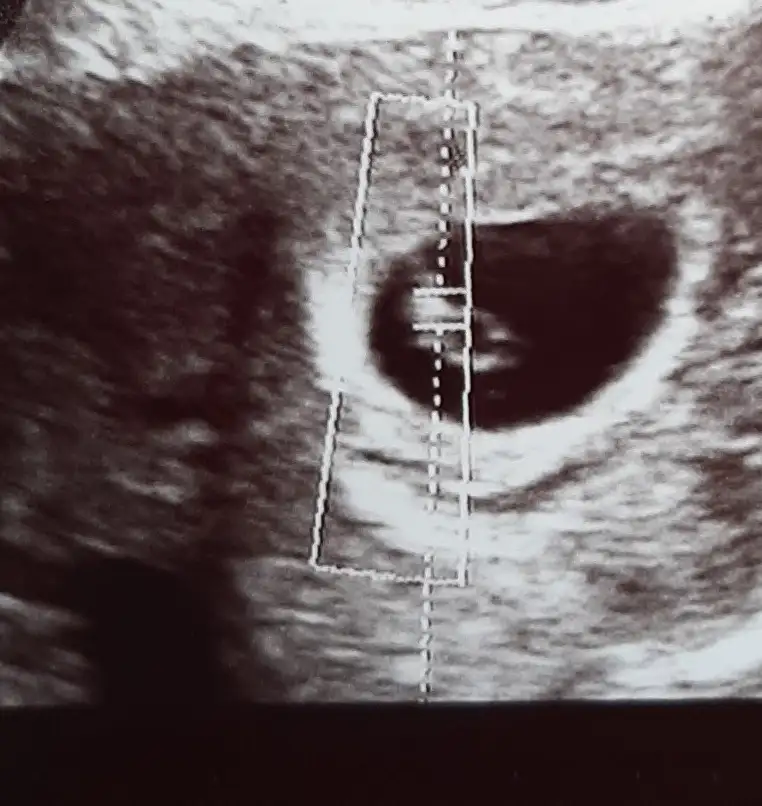

Bundan önce yavaş mı arttı böyle beta değerlerinizKizlar 6+2 hamileyim kese görünmemişti 18 subatta 3800 cıktı beta bugun 25 subat 10.000 kese minik ama cok net birşey söylemiyorlar kanamam oldu cok az hastanedeyim 10.000 cok mu az artis lütfen fikirlerinize ihtiyacım var dr ameliyattaymış çıkmasını bekliyorum

Tebrik ederim evet vajinal görünürdü neden baktırmak istemediniz?Merhabalar kızlar dün çift çizgi testten sonra 1209beta ile gebe olduğumu öğrendim. Vajinal ultrasonda bakalım dedi ben istemedim istemiyosan bakmayalım ozaman pazartesi gebe kliniğine gel dedii.Çok korkuyorum dış gebelik olursa kese görünmezse kalp atışı olmazsa diye. Pazartesi tam 5.hafta sizce kese karından görülür müü? Sata göre 4+3 benide listeye ekler misiniz.Kedilervekitaplar